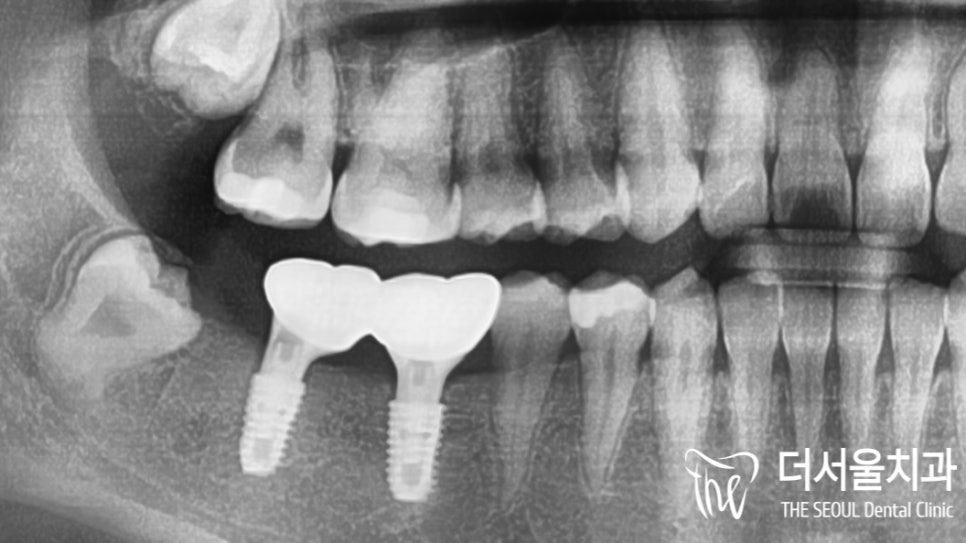

별다른 문제 없이

치조골에 단단히 심어진 모습입니다.

픽스쳐를 심고 나서

치유지대주(healing abutment)까지 체결을 도왔습니다.

이제 잇몸이 형성되고 회복될 수 있도록

기다리는 인내의 시간을 가져야 됩니다^^

드디어 20대 임플란트 환자의

최종보철을 올려드릴 날이 밝았습니다.

지르코니아로 제작된 크라운을 올려드린 모습입니다.

교합은 물론이며 주변에 있는 인접치들과

잘 어울리고 있는 모습이죠~?